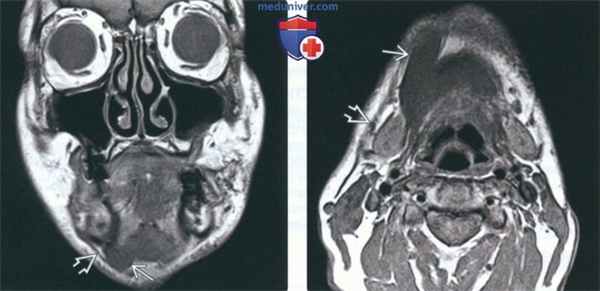

(Слева) На корональной МРТ (Т1 ВИ) переднее брюшко двубрюшной мышцы и подкожная мышца шеи справа не изменены. Челюстно-подъязычная мышца и подкожная мышца шеи слева не видны в результате хронического повреждения ЧМН V3 и ЧМН VII, соответственно.

(Справа) На аксиальной МРТ (Т1 ВИ) у этого же пациента отсутствуют патологические изменения переднего брюшка двубрюшной мышцы В и подкожной мышцы шеи& справа. Обе мышцы слева подверглись жировой атрофии, вследствие чего не видны. Злокачественная опухоль основания черепа поражает овальное отверстие и ямку коленчатого ганглия.